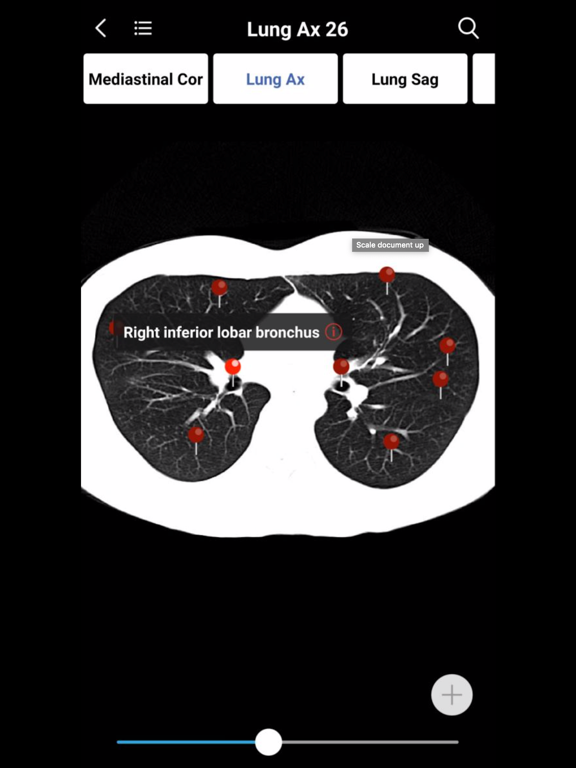

1. Normal imaging anatomy atlases which have the detailed structure labeling in coronal, sagittal, axis section. You can search any imaging structures conveniently at any time. Currently all imaging atlases’ images are JEPG format,  and they will be replaced by DICOM images very soon. This means you can to adjust the window width and window location of all images in the atlases. It's unbelievable!

6. MedImaging covers the entire body: Brain, Head, Neck, Spine, Chest, Chest, Pelvis, Limbs X-ray, CT, MRI, and in the future will include ultrasound and all commonly used atlas.